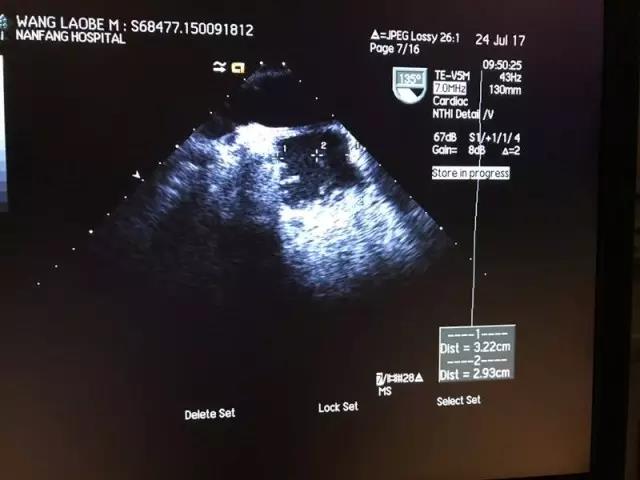

该病例为70岁男性,气促、喘息1周余,诊断为心律失常(心房颤动),入院评估CHA2DS2-VASc评分为3分。术前心脏彩超检查左房耳横径约32.2mm,前后径约29.3mm,左心耳为双叶结构,呈菜花状,左心房及左房耳内未见血栓影。

(术前经食道超声检查左心耳)